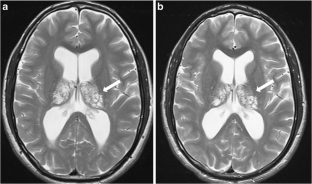

Fig. 1